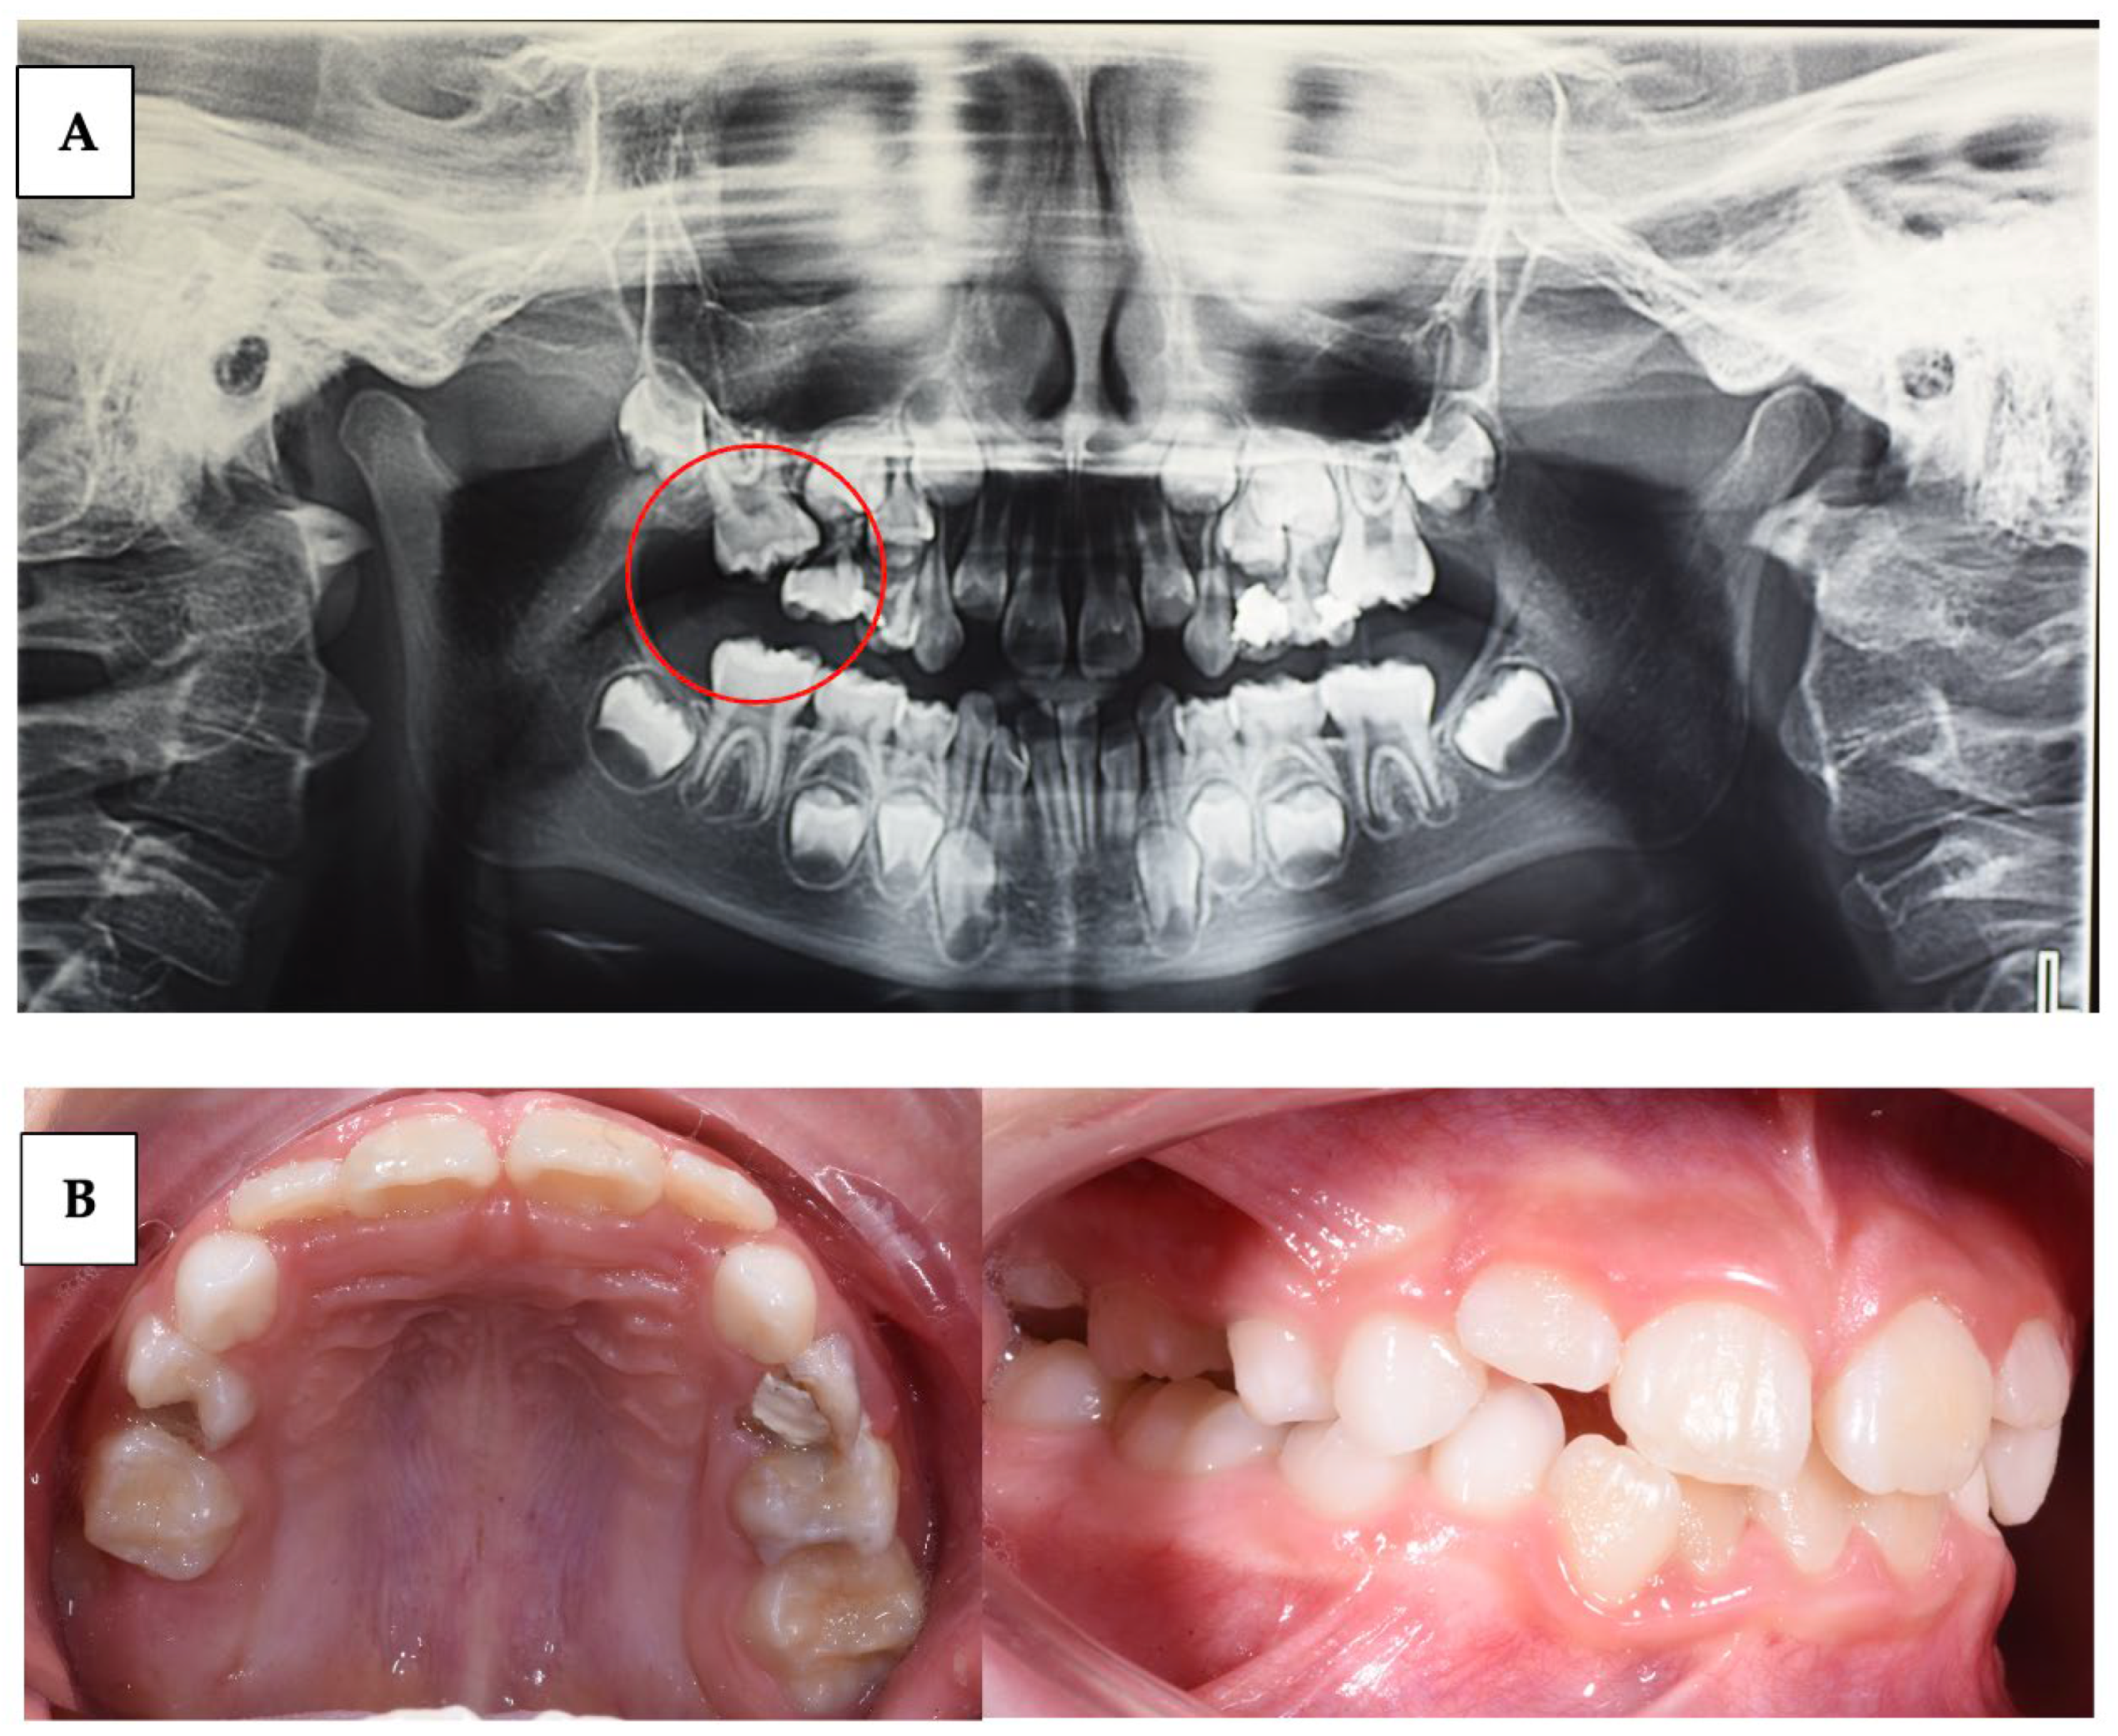

| Stellzig-Eisenhauer et al. (2010) [19] | Case series | 15 | Identify a genetically verified diagnosis of PFE to improve treatment choice. | Clinical and Molecular Genetics Analysis | Molecular genetic analysis of the PTHR1 gene revealed three distinct heterozygous mutations. Unaffected patients exhibited no mutations. |

| Wagner et al. (2023) [59] | Case series | 3 | Describe the variability of clinical presentations of PFE associated with pathogenic variants of PTHR1 | Clinical examination, radiological examination, and molecular DNA testing | Multidisciplinary complex treatment, from child to adulthood. |